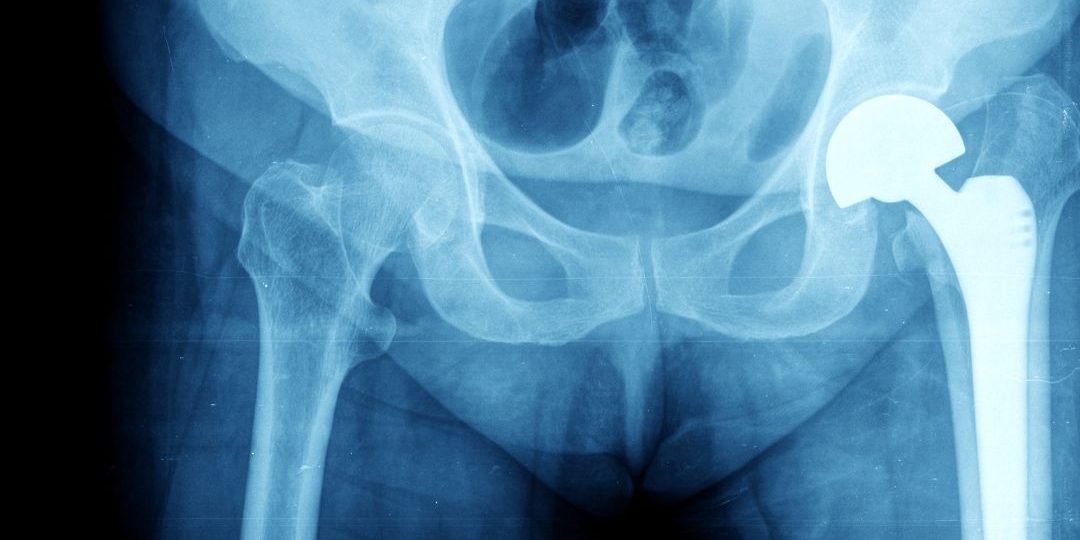

Por un lado, encontramos la prótesis total. Está compuesta por un vástago que une la prótesis al fémur, un cotilo que la fija a la pelvis y dos componentes que la articulan entre sí. Suelen utilizarse en los casos de artrosis o desgaste articular.

A su vez, tenemos la prótesis parcial. Se fija igual que la prótesis total, pero la cabeza femoral articula directamente contra la pelvis. Es por ello que se emplea en fracturas del fémur donde el acetábulo puede o no estar desgastado.